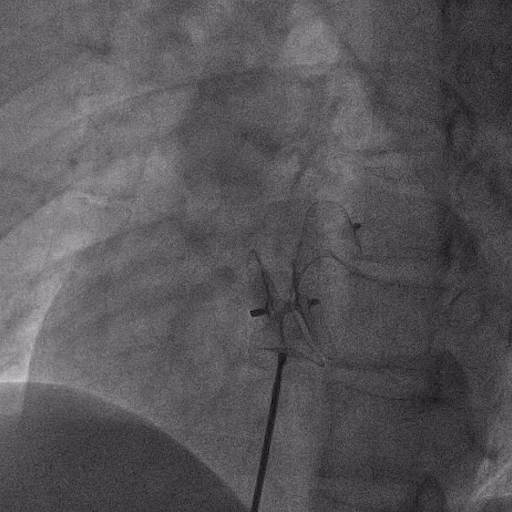

在獲得患者同意后,1月12日,尚福軍主任為患者進(jìn)行了PFO封堵術(shù)。術(shù)中造影可見封堵器殘余漏,尚福軍主任用精湛的技藝,順利通過封堵器殘余漏裂縫,將右心導(dǎo)管從右房送入左房,且順利到達(dá)肺靜脈;遂行卵圓孔未閉封堵術(shù)后殘余漏再次封堵;且完美釋放PFO封堵器,可見兩封堵器呈“馬蹄蓮”狀,再次術(shù)中造影未見殘余漏。

術(shù)后,小鞏生命體征平穩(wěn)。相關(guān)檢查顯示正常,且術(shù)后完善心臟彩超及發(fā)泡試驗,可見封堵器位置良好,未見右向左分流,發(fā)泡試驗陰性。